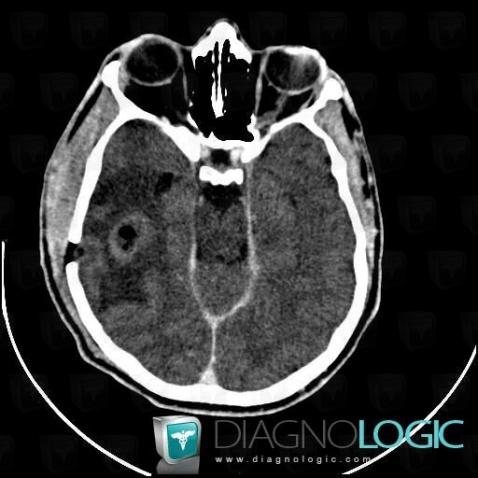

Abscess, Cerebral hemispheres, CT

Here is the specific information in the key image above:

- Diagnosis Abscess, Location(s) Cerebral hemispheres, with gamuts Hypodense intracerebral lesion on noncontrast CT